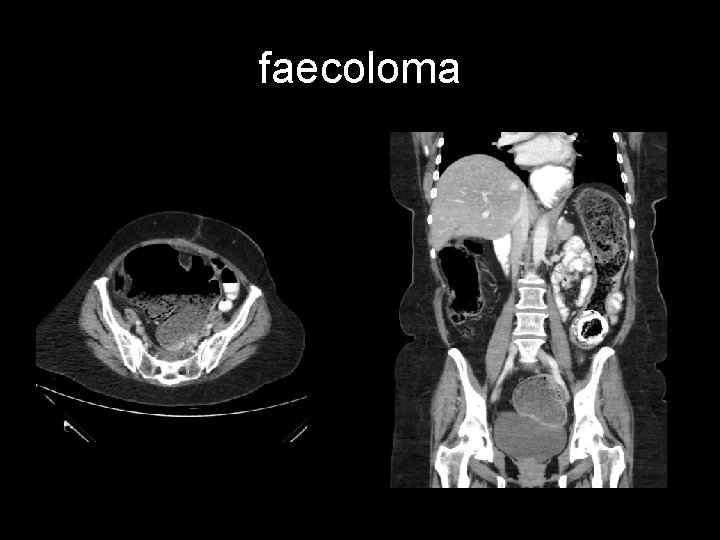

Large bowel obstruction (LBO) are often impressive on imaging, on account of the ability of the large bowel to massively distend. This condition requires prompt diagnosis and treatment. Large bowel obstructions are far less common than small bowel obstructions, accounting for only 20% of all bowel obstructions. Large bowel obstructions is age-dependant the most common cause is colonic cancer (50 -60%), typically in the sigmoid The second most common cause in adults is acute diverticulitis (involving the sigmoid colon). Together, obstructing tumours and acute diverticulitis account for 90% of all causes of large bowel obstruction.

faecoloma